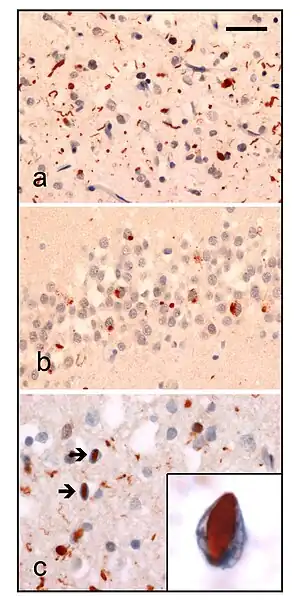

| Neuropathologic analysis of brain tissue from FTLD-TDP patients. Ubiquitin immunohistochemistry in cases of familial FTLD-TDP demonstrates staining of (a) neurites and neuronal cytoplasmic inclusions in the superficial cerebral neocortex, (b) neuronal cytoplasmic inclusions in hippocampal dentate granule cells, and (c) neuronal intranuclear inclusions in the cerebral neocortex (arrows). Scale bar; (a) and (b) 40 μm, (c) 25 μm, insert 6 μm. | |

- Type A presents with many small neurites and neuronal cytoplasmic inclusion bodies in the upper (superficial) cortical layers. Bar-like neuronal intranuclear inclusions can also be seen they are fewer in number.

- Type B presents with many neuronal and glial cytoplasmic inclusions in both the upper (superficial) and lower (deep) cortical layers, and lower motor neurons. However neuronal intranuclear inclusions are rare or absent. This is often associated with ALS and C9ORF72 mutations (see next section).

- Type C presents many long neuritic profiles found in the superficial cortical laminae, very few or no neuronal cytoplasmic inclusions, neuronal intranuclear inclusions or glial cytoplasmic inclusions. This is often associated with semantic dementia.

- Type D presents with many neuronal intranuclear inclusions and dystrophic neurites, and an unusual absence of inclusions in the granule cell layer of the hippocampus. Type D is associated with VCP mutations.